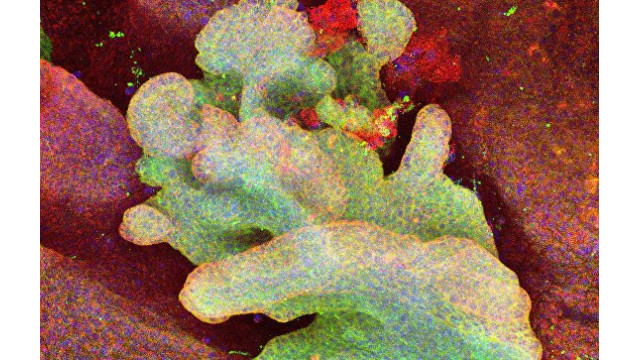

УЧЕНЫЕ ВПЕРВЫЕ УВИДЕЛИ, КАК "РОЖДАЕТСЯ" РАК КОЖИ